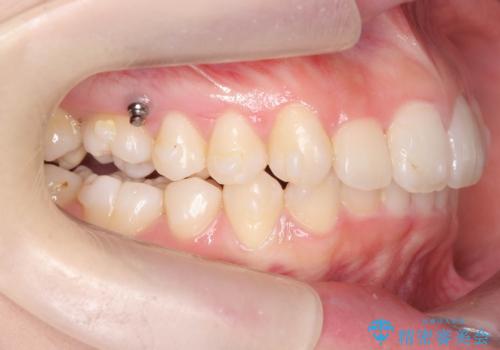

途中顎位が変わり、マイクロインプラントを併用した上顎臼歯の遠心移動が必要となったため治療が長期化しました。